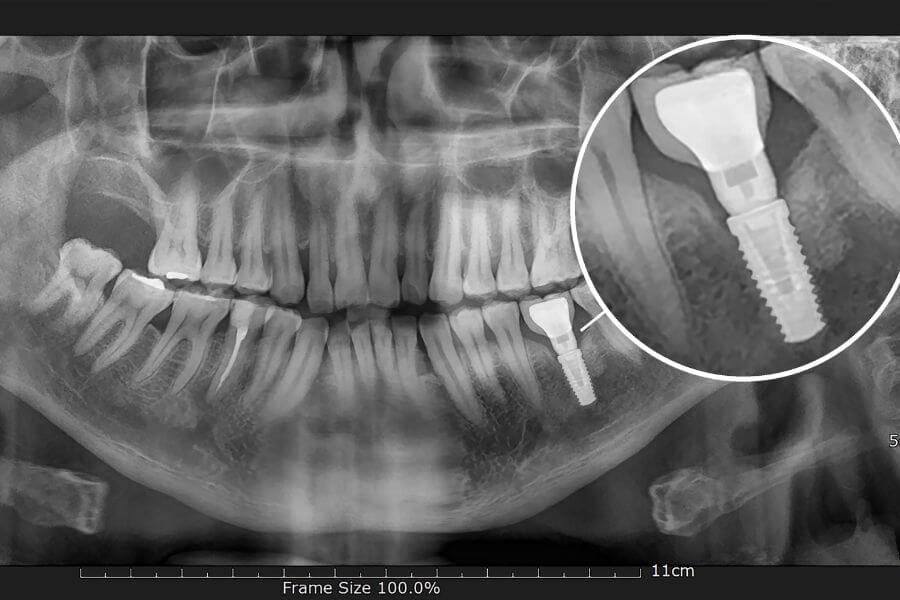

L'impianto dentale consiste nella sostituzione della radice naturale del dente mancante con una vite in titanio inserita nelle ossa mascellari. All'impianto è applicato un perno moncone che sostiene la corona avvitata o cementata; in questo modo viene ricreato il dente nella sua struttura interna ed esterna.

radiografia impianto dentale in titanio